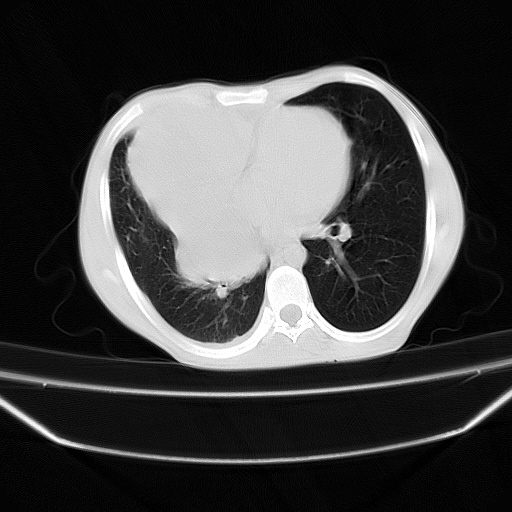

以下是引用zjzjr在2008-7-20 12:57:00的发言:[br]考虑为生殖源性肿瘤(内胚窦瘤),侵袭性胸腺瘤可能性大;右侧少量胸腔积液。

以下是引用xinliheng001在2008-7-20 21:17:00的发言:[br]右纵隔巨大分叶状软组织均质密度肿块,右上肺叶受压明显,纵隔右移、胸膜受累有少量积液和结节样增厚。应增强扫描一定会有更具诊断价值的信息。

以下是引用xinliheng001在2008-7-20 21:17:00的发言:[br]右纵隔巨大分叶状软组织均质密度肿块,右上肺叶受压明显,纵隔右移、胸膜受累有少量积液和结节样增厚。应增强扫描一定会有更具诊断价值的信息。